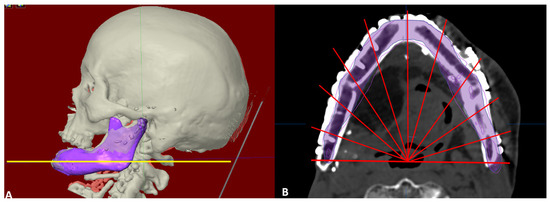

2.4. Evaluation of Accuracy of Planning

The evaluation phase in postoperative period started with a repeat CT scan after six months of reconstructive surgery and involved superimposition of postoperative images with virtually reconstructed mandible in the computer planning (Figure 8, Figure 9 and Figure 10). The 3D craniofacial image was reoriented with counterclockwise pitch rotation to allow the whole mandible from the right to the left angle be seen in one axial 2D view. In the 2D view, a section through the mid-way of chin and parallel to the lower mandibular border was selected for measurement (Figure 11A). The entire length was divided into ten segments, each separated with an angulation of eighteen degrees from the base line joining the two angles, resulting into 11 points of measurement (Figure 11B). The linear discrepancies between virtually planned position and the buccal aspect of actual bone position were measured. The mean differences in the distance and the standard deviation were consequently calculated. The differences in mean between the three categories were also calculated to compare the accuracy of reconstruction.

Figure 11.

Evaluation of accuracy of reconstruction with virtual plan. (A) Reconstructed mandible superimposed over virtual plan, a section through the mid-way of chin and parallel to the lower mandibular border selected for measurement (yellow line). (B) The length of reconstruction divided into ten segments by eleven red lines, eighteen degrees each from center of angle-angle baseline and discrepancy measured at eleven points at the outer border (excluding the reconstruction plate).